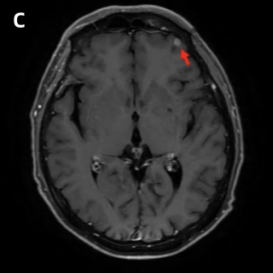

头颅增强MRI及DWI:左侧额叶见一结节样强化灶,考虑转移瘤(图2)。

图2 初诊时颅脑病灶(红色箭头指向病灶)[1]

头颅增强MRI及DWI:左侧额叶原有病灶较前增大(图4C),左侧颞枕叶交界区见新发病灶(图4D)。

图4 右肺病灶、左侧腋窝淋巴结及颅脑病灶复查结果(红色箭头指向病灶)[1]